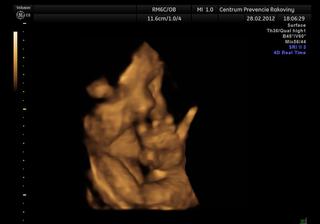

@mirkave my sme v 29 tyzdni vazili cca kilecko..doktor na sone povedal,ze sme trosku mensi,ale v pohode a doktorka povedala,ze sme mooc maly..tak si tiez mozem vybrat 🙂 vcera sme boli na 3d sone aspon trosku sa ukazala..a licka ma ako tatransky svistik, tak urcite podvyzivena nebude 🙂))

Robil mi aj 3d sono, ale mala si dala nohu pred tvar, tak mam fotku ucha 😀